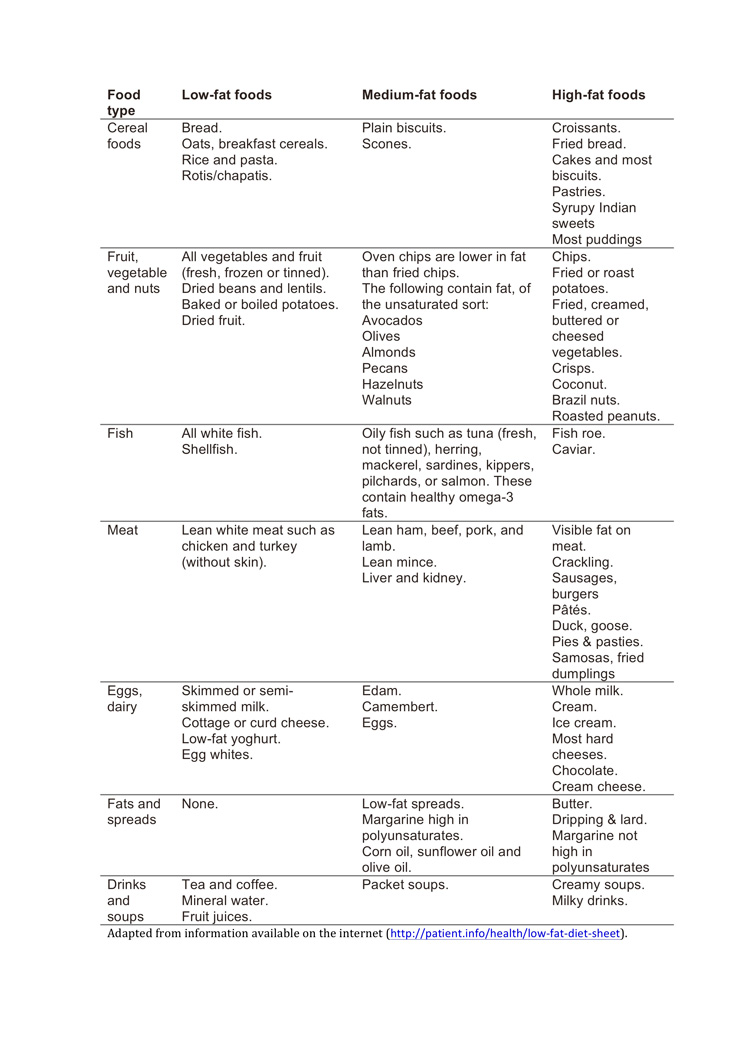

Is there a particular diet I should follow if I have gallstones?If certain fatty foods have triggered your attacks of pain, you should obviously avoid those. In general, you will be better off if you adopt a low fat diet. This will not get rid of your gallstones, but may reduce the severity and frequency of your attacks of pain. Here are some tips:

What to eat and what not to eat- Eat mainly plants; less meat

- Eat fish or poultry in preference to red meat, as red meat contains more fat.

- Eat home cooked food (where you can control what goes in, rather than purchased or processed foods).

- When buying food, look at the fat content (over 17.5% is high fat content; 3-17.5% is moderate fat content; less than 3% is low fat; see the next page)

- Avoid butter, cream, lard and high-fat cheese.

- Cut down on oily curries, fish and chips, fry-ups, burgers.

- Cut down on cakes, pastries, croissants, cookies and ice cream. Nothing needs to be treated as totally forbidden. A small portion of something as an occasional treat is perfectly OK.

- But if there is something specific that triggers your attacks of pain (often this can be cheesy pasta, burgers, fry-up breakfasts, take-out curries), AVOID that at all costs.

How to cook- Trim all fat and skin off meat

- When cooking vegetables or meat, try to boil, steam, grill, bake or shallow-fry in a non-stick pan rather than deep-fry or cook in a rich sauce.

- Try and use low-fat alternatives where they exist. When baking cakes, half of the butter can usually be replaced by zero fat yogurt,

Below is a list of the fat content of common food items: